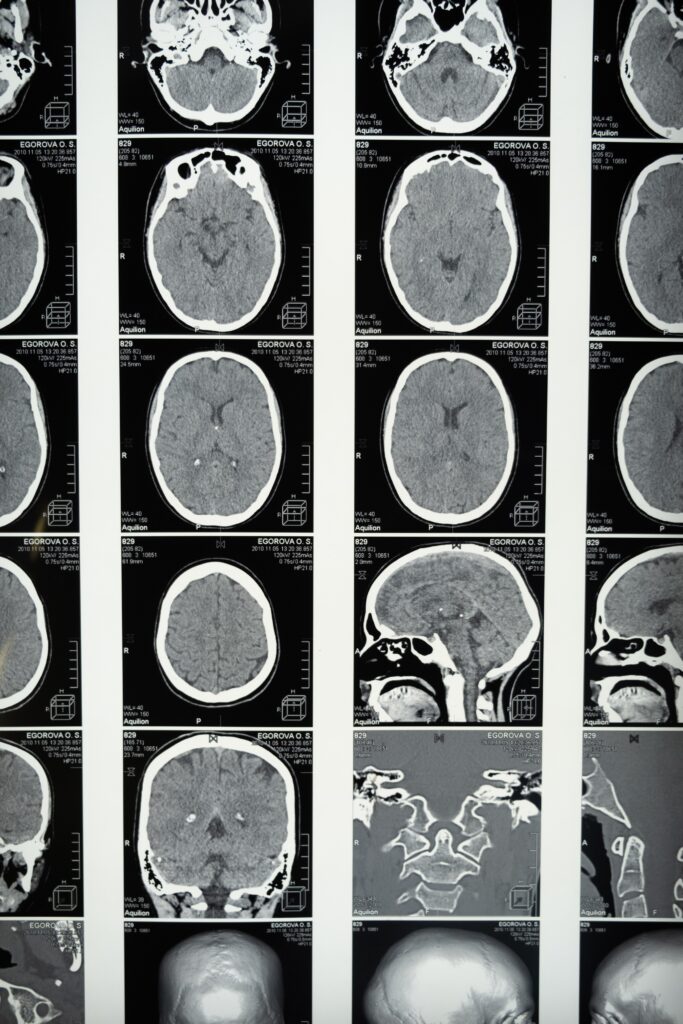

El enigma de los hemisferios cerebrales en el lenguaje

El cerebro humano, dividido en dos hemisferios, muestra una notable especialización en sus funciones. En este contexto, el hemisferio izquierdo es comúnmente reconocido como dominante en tareas relacionadas con el habla, la lectura y la escritura. En consecuencia, se asume que lesiones en tal región conllevan la pérdida de tales funciones. Sin embargo, la neurociencia ha revelado que la plasticidad cerebral, capacidad del cerebro para reorganizarse y adaptarse, desempeña un papel crucial.

Plasticidad cerebral y recuperación

Tal es así, que estudios han demostrado que, especialmente en edades tempranas, el cerebro puede compensar las lesiones en el hemisferio izquierdo y recuperar algunas funciones relacionadas con el lenguaje. Y es que, no hay que olvidar que la plasticidad disminuye con la edad, lo que sugiere que el momento en que se produce la lesión desempeña un papel esencial en la recuperación de estas habilidades lingüísticas. La comprensión de la lateralización del lenguaje y su relación con la plasticidad cerebral es un área de investigación en constante evolución que arroja luz sobre la capacidad del cerebro humano para adaptarse y recuperar funciones cruciales en situaciones adversas (Bishop et al., 2015).